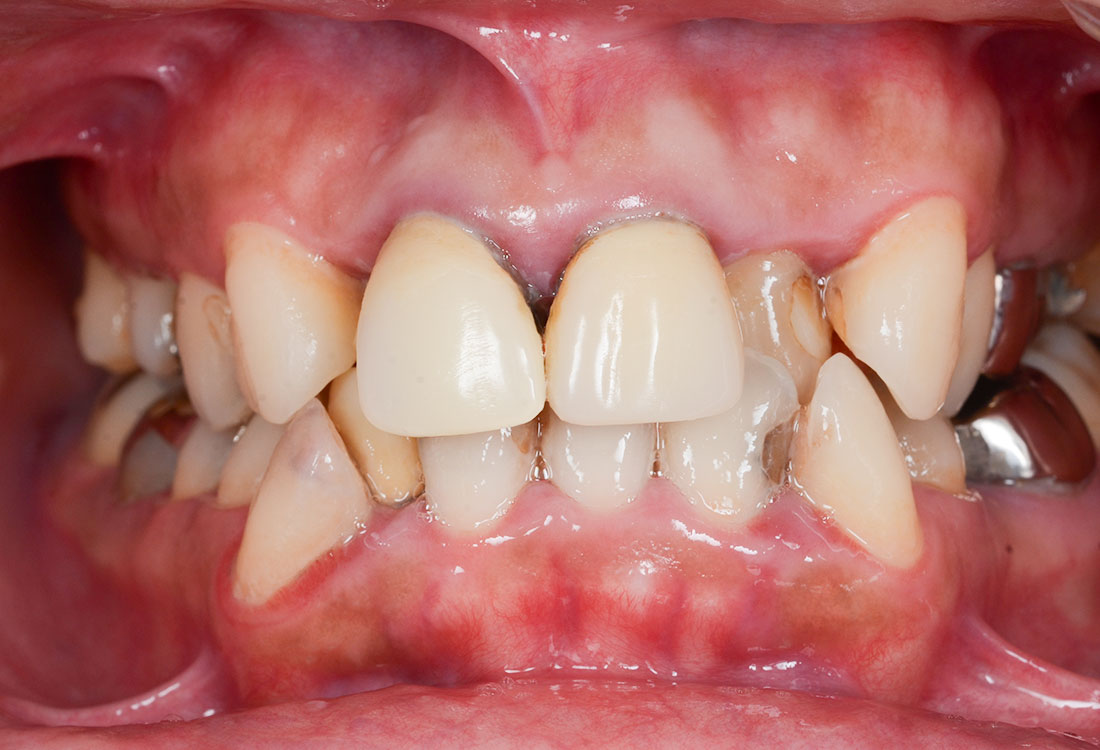

ご相談内容

- 歯並びが気になる

- 矯正をする時間が取れないので被せ物で治していきたい

治療前